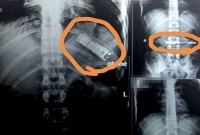

৭ মাস যাবৎ যুবকের পেটে আস্ত মোবাইল ফোন, চিকিৎসকদের চোখ কপালে!

আন্তর্জাতিক ডেস্ক : মানুষের পেটের ভেতর আস্ত একটি মোবাইল ফোন। অবা'ক শোনা গেলেও এটাই সত্যি। গত সাত মাস যাবৎ মোবাইল ফোনটি ছিল এক যুবকের পেটের মধ্যেই। সম্প্রতি যুবকের পেটে করা... ...বিস্তারিত»